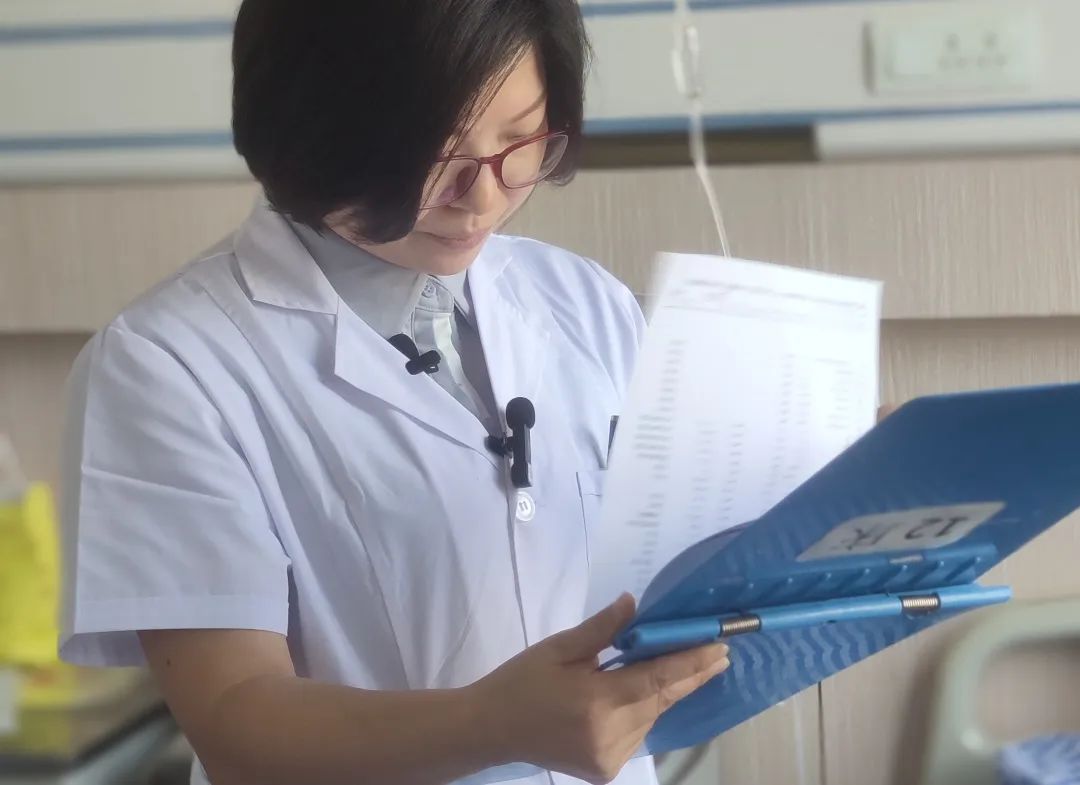

大家好,我是成都西部痛风风医院风湿免疫科医生张利君。在我查房的过程中,相信大家也看到了不少长出痛风石的痛风患者,其中有一部分患者在得了痛风石后,还不做好药物治疗和自我管理等,这让他们的痛风石迅速发展,导致后期痛风石发展到关节变形、以及关节出现破坏,以至于需要截肢治疗。痛风石到底是怎么对我们的关节造成伤害的?痛风石还会造成什么伤害?患上痛风石后又需要做什么来预防关节破坏?张医生为大家一一解答。